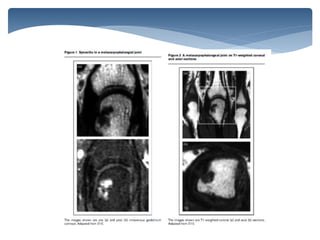

MRI and Miniarthroscopy of MCP Joints in RA . Arthritis Rheum 2001; 44:2492–2502.

TI + contrast

類風溼性關節炎在核磁共振下可觀

察到的病理變化

 Synovitis 滑膜炎

 Tenosynovitis 肌腱滑膜炎

 Bone Erosions 骨侵蝕

 Bone Marrow Edema 骨質發炎水腫

 Bursitis 滑囊炎

 contrast-enhanced MRI depicted more abnormalities

within the osseous structures of the rheumatoid wrist

than corresponding fat-suppressed T2-weighted fast

spin-echo imaging.

Contrast-enhanced T1-weighted images are considered

more sensitive and specific in the assessment of acute

synovitis

AJR:187, August 2006

Tenosynovitis

AJR:189, December 2007

T1FS + C

Effusion: dark(T1) ; bone: dark(T1 white -> T1FS :no fat signals, dark)

Synovitis, contrast median: water

Contrast-enhanced axial T1-

weighted fat-saturated MR image